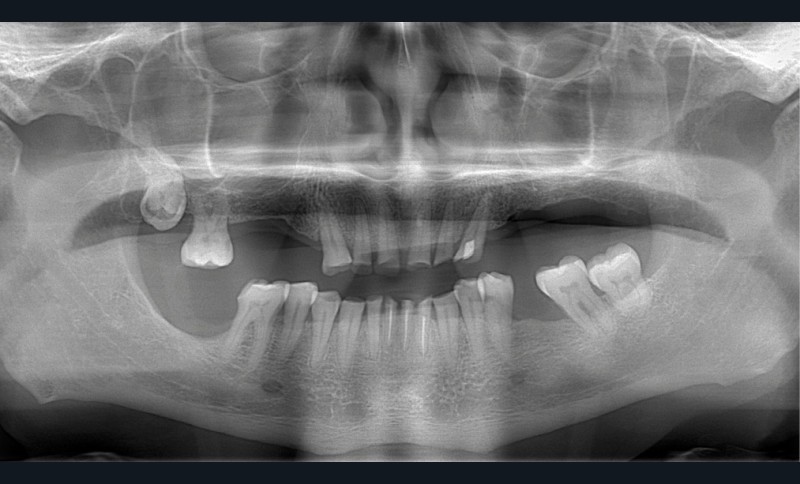

Un patient de 68 ans arrive au cabinet ; il présente de nombreux édentements ainsi qu’une usure parafonctionnelle très avancée.

Il consulte en urgence pour une douleur sur la 23 dont le traitement endodontique s’impose. Il relate également des difficultés croissantes pour s’alimenter.

• L’examen intrabuccal montre de nombreux édentements non compensés (14, 15, 16, 24, 25, 26, 27, 47 et 36) ainsi que des pertes de substance très importantes, notamment dans le secteur antérieur.

Une attrition sévère, couplée à une occlusion sans calage postérieur, a engendré des difficultés pour s’alimenter.

La perte de dimension verticale par usure prématurée nécessite d’augmenter cette dernière de façon importante, et en une seule fois.